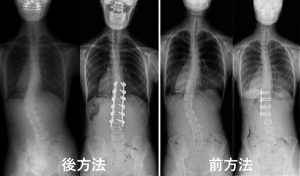

カーブの頂点が腰椎に位置する場合に適応となりますが、カーブパターンによっては後方法を選択する場合もあります。前方法では、肋骨に沿って背骨の側面に到達して矯正します。後方法に比べて短い範囲で固定が可能であり、当科の金田清志第4代教授が開発したインプラントは米国FDA(食品医薬品局)に認可され、世界的な普及に貢献した歴史があります。後方法、前方法どちらであっても手術1か月前から北大病院輸血部で自分の血をあらかじめ貯血(自己血貯血)し、手術中に出た血も回収して再利用する(術中回収血輸血)ため、他人の血を輸血することはほとんどありません。